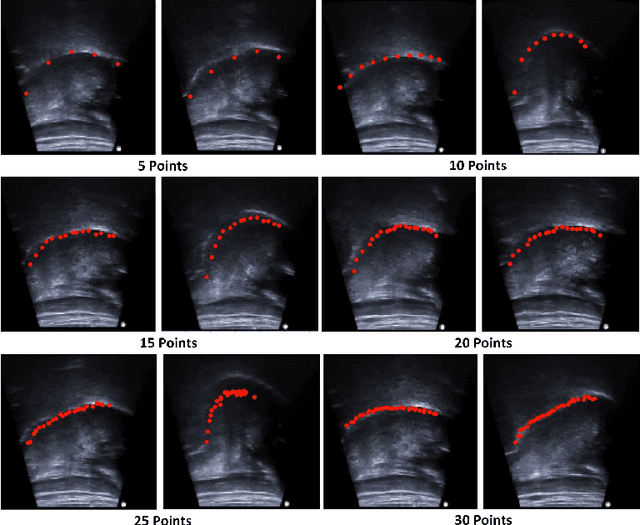

Abstract:One usage of medical ultrasound imaging is to visualize and characterize human tongue shape and motion during a real-time speech to study healthy or impaired speech production. Due to the low-contrast characteristic and noisy nature of ultrasound images, it might require expertise for non-expert users to recognize tongue gestures in applications such as visual training of a second language. Moreover, quantitative analysis of tongue motion needs the tongue dorsum contour to be extracted, tracked, and visualized. Manual tongue contour extraction is a cumbersome, subjective, and error-prone task. Furthermore, it is not a feasible solution for real-time applications. The growth of deep learning has been vigorously exploited in various computer vision tasks, including ultrasound tongue contour tracking. In the current methods, the process of tongue contour extraction comprises two steps of image segmentation and post-processing. This paper presents a new novel approach of automatic and real-time tongue contour tracking using deep neural networks. In the proposed method, instead of the two-step procedure, landmarks of the tongue surface are tracked. This novel idea enables researchers in this filed to benefits from available previously annotated databases to achieve high accuracy results. Our experiment disclosed the outstanding performances of the proposed technique in terms of generalization, performance, and accuracy.

Abstract:The progress of deep convolutional neural networks has been successfully exploited in various real-time computer vision tasks such as image classification and segmentation. Owing to the development of computational units, availability of digital datasets, and improved performance of deep learning models, fully automatic and accurate tracking of tongue contours in real-time ultrasound data became practical only in recent years. Recent studies have shown that the performance of deep learning techniques is significant in the tracking of ultrasound tongue contours in real-time applications such as pronunciation training using multimodal ultrasound-enhanced approaches. Due to the high correlation between ultrasound tongue datasets, it is feasible to have a general model that accomplishes automatic tongue tracking for almost all datasets. In this paper, we proposed a deep learning model comprises of a convolutional module mimicking the peripheral vision ability of the human eye to handle real-time, accurate, and fully automatic tongue contour tracking tasks, applicable for almost all primary ultrasound tongue datasets. Qualitative and quantitative assessment of IrisNet on different ultrasound tongue datasets and PASCAL VOC2012 revealed its outstanding generalization achievement in compare with similar techniques.

Abstract:Ultrasound imaging is safe, relatively affordable, and capable of real-time performance. One application of this technology is to visualize and to characterize human tongue shape and motion during a real-time speech to study healthy or impaired speech production. Due to the noisy nature of ultrasound images with low-contrast characteristic, it might require expertise for non-expert users to recognize organ shape such as tongue surface (dorsum). To alleviate this difficulty for quantitative analysis of tongue shape and motion, tongue surface can be extracted, tracked, and visualized instead of the whole tongue region. Delineating the tongue surface from each frame is a cumbersome, subjective, and error-prone task. Furthermore, the rapidity and complexity of tongue gestures have made it a challenging task, and manual segmentation is not a feasible solution for real-time applications. Employing the power of state-of-the-art deep neural network models and training techniques, it is feasible to implement new fully-automatic, accurate, and robust segmentation methods with the capability of real-time performance, applicable for tracking of the tongue contours during the speech. This paper presents two novel deep neural network models named BowNet and wBowNet benefits from the ability of global prediction of decoding-encoding models, with integrated multi-scale contextual information, and capability of full-resolution (local) extraction of dilated convolutions. Experimental results using several ultrasound tongue image datasets revealed that the combination of both localization and globalization searching could improve prediction result significantly. Assessment of BowNet models using both qualitatively and quantitatively studies showed them outstanding achievements in terms of accuracy and robustness in comparison with similar techniques.